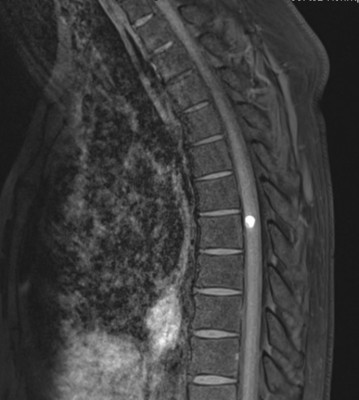

Resonancia Magnética de Columna

Envíado por Dr. José Rafael Chang Calero